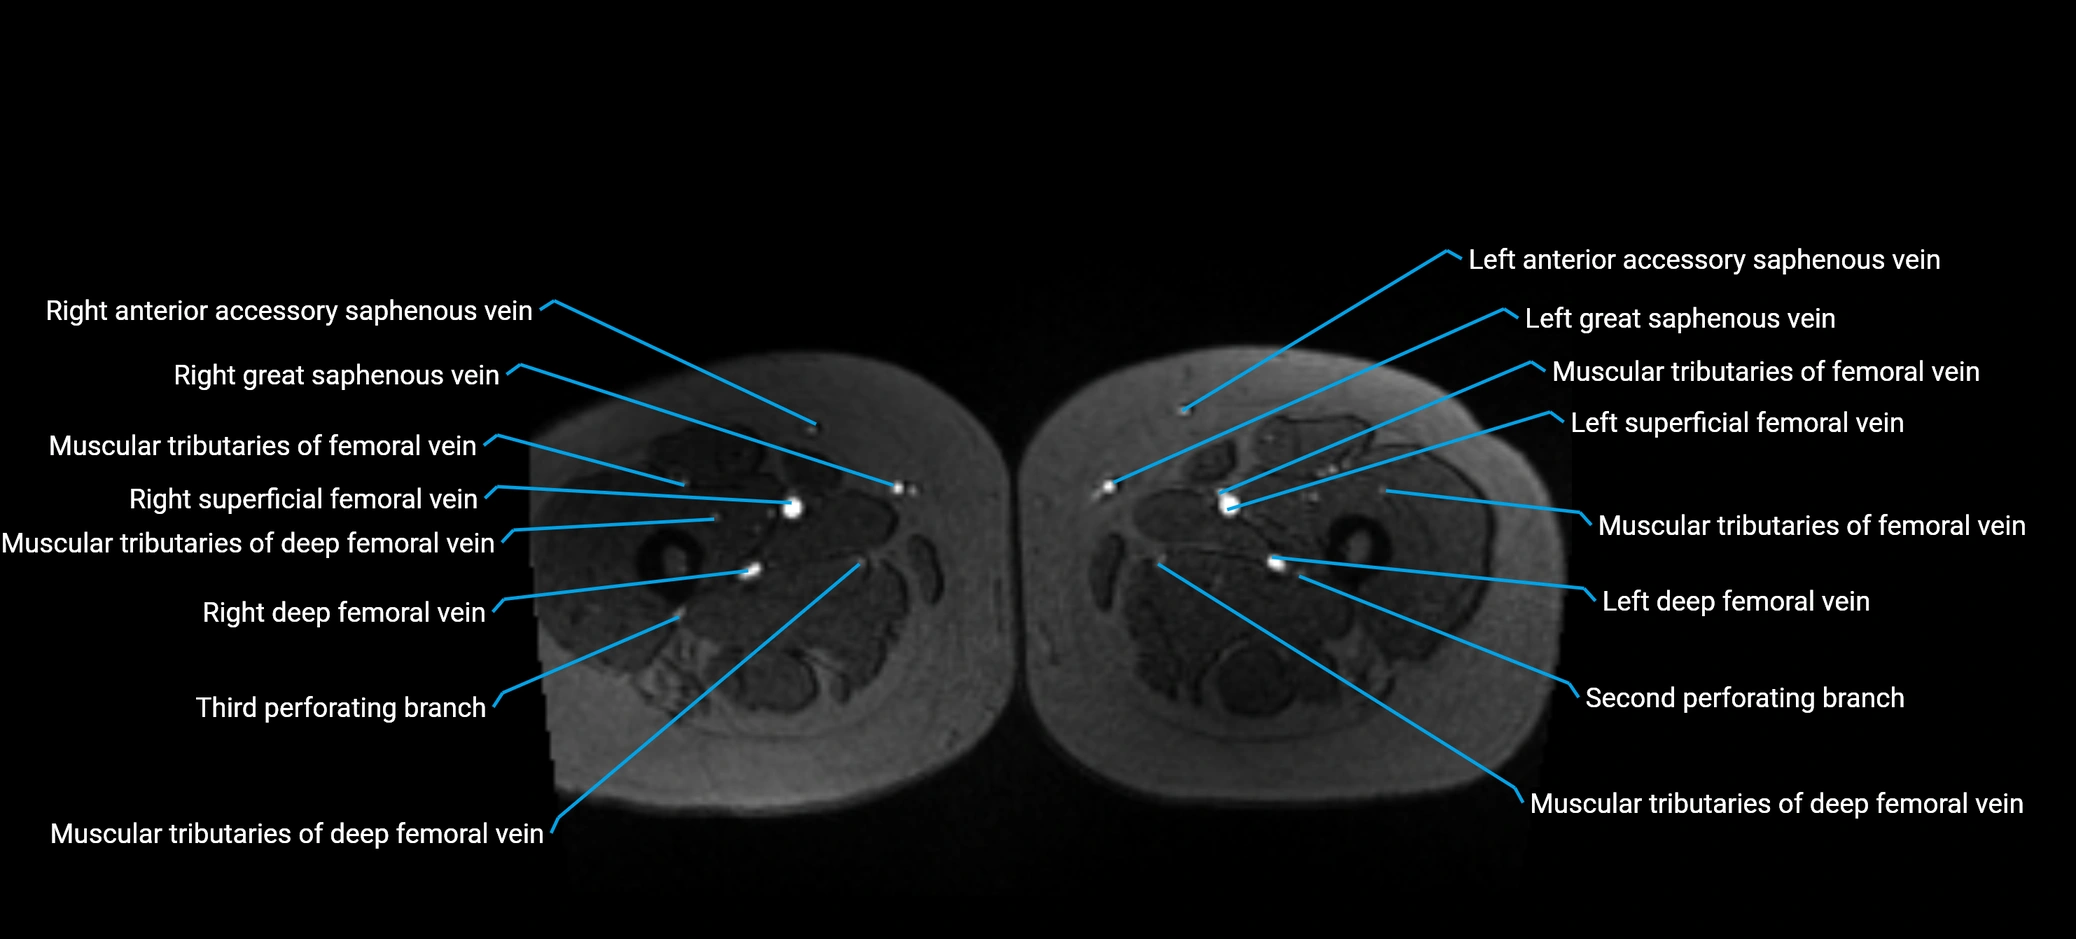

MRI image

image